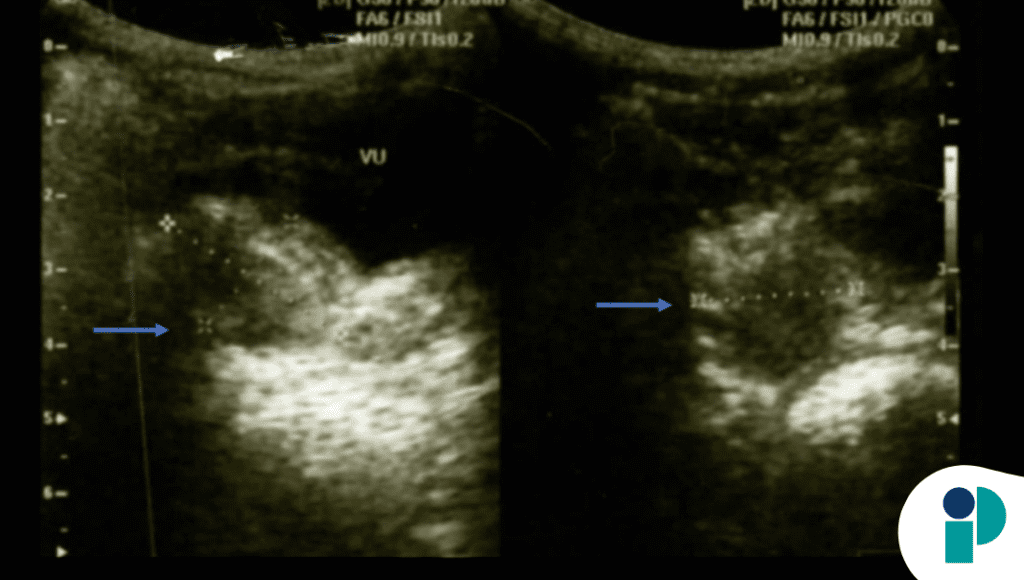

Los estudios complementarios reforzaron este hallazgo. La ecografía pélvica mostró útero y ovarios con características prepuberales, sin masas, quistes ni anomalías estructurales. Además, los niveles hormonales —incluyendo hormona luteinizante y foliculoestimulante— se encontraban dentro de rangos normales para la edad, descartando activación endocrina.